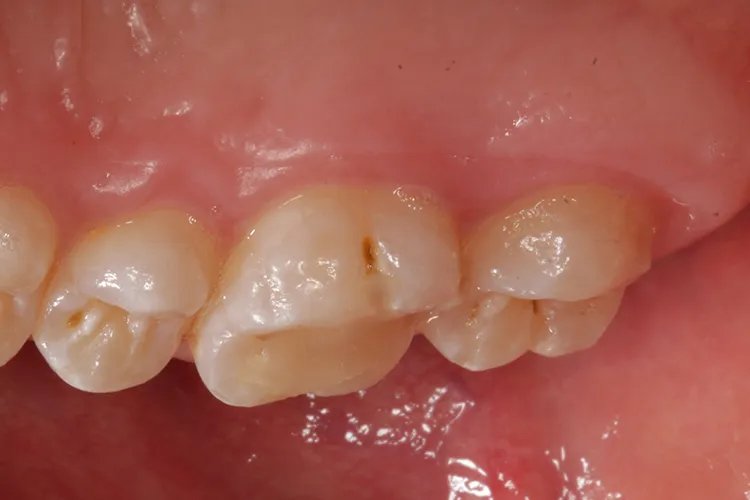

概述蛀牙牙虫在医学上称为龋齿,主要表现为坏牙颜色改变、外形缺损、质地改变以及患者感觉的变化。迄今为止龋齿的病因尚未完全研究清楚,但主要与致龋菌和致病的牙菌斑环境,同时口腔中含有细菌代谢的底物有关。症状坏牙颜色的改变病变部位表面粗糙,光泽消失,早期呈白恶色,进一步着色还可以呈棕黄色或黑褐色。

外形缺损是龋齿最显著的临床特征,形成了牙体组织的实质性缺损。临床上可以看到、探到或检查到龋洞。

质地的改变龋造成的牙体组织的实质性缺损称为龋洞。龋洞中充满感染脱矿的牙体组织和食物碎屑,质地松软,容易与正常组织区别。